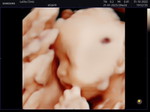

สายสะดือพันคอ3รอบ

ตอนนี้ตั้งท้องน้องได้32weeksแล้ว คุณหมอบอกสายสะดือพันคอ3รอบ ส่วนตัวเราเป็นคนท้องเล็ก แต่น้องน้ำหนักตามเกณฑ์ค่ะน้ำคร่ำปกติ เราก็กังวลว่าน้องจะดิ้นจนหลุดเองได้ไหมเพราะพื้นที่มันน้อยขึ้นทุกวันๆ มีคุณแม่ท่านไหนเคยเจอเหตุการณ์แบบนี้บ้างไหมคะ ขอคำแนะนำหน่อยค่ะ เรากังวลมากๆเลย #ขอบคุณสำหรับคำตอบค่ะ